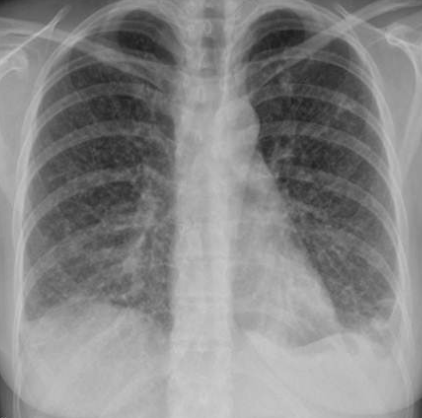

What is the abnormality in CXR? Hilar lymphadenopathy (enlarged lymph nodes in the hila of both lungs)

-

What is the most likely diagnosis? Sarcoidosis; lump

Bilateral Hilar Lymphadenopathy: Causes

| Category | Causes |

|---|---|

| Sarcoidosis | Sarcoidosis |

| Infection | * Tuberculosis * Fungal infection * Mycoplasma * Intestinal Lipodystrophy (Whipple’s disease) |

| Malignancy | * Lymphoma * Carcinoma * Mediastinal tumors |

| Inorganic dust disease | * Silicosis * Berylliosis |

| Extrinsic allergic alveolitis | * Such as bird fancier’s lung |

| Less Common Causes | * Churg-Strauss syndrome * Human immunodeficiency virus * Extrinsic allergic alveolitis * Adult-onset Still’s disease |